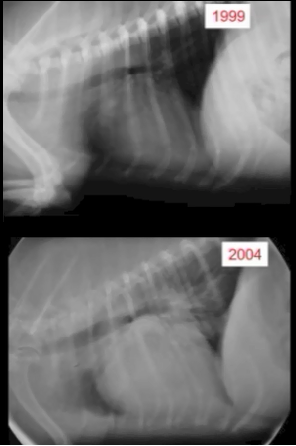

A dilemma which veterinary cardiologists face when performing an initial echo scan of the heart of a MVD-affected dog is how to determine upon that initial scan whether the LV still is of normal size or already has begun to enlarge. Researchers attempt to resolve that difficulty by predicting the size of normal-sized LVs. In the case of the LV, it has been determined that the dog's body weight plays a role in establishing normal reference ranges for LVs.

Thus, in a May 2004 article, involving 494 normal (meaning no MVD murmurs) dogs of 8 breeds, the authors devised an allometric equation to determine an "appropriate" body weight exponent to determine normal-sized LV dimensions on a breed-wide, and even species-wide, basis. They arrived at a range of exponents between 0.22 and 0.35 and settled upon 0.294. The image below demonstrates how they applied that exponent in their calculations. They named that resulting dimension, "left ventricular end diastolic diameter normalized to body weight" or LVIDdN for short. Based upon that 0.294 exponent, they concluded that, "If the result is between 1.27 and 1.85, the [LV] value is within the normal prediction interval for this study." These researchers acknowledged that:

"Not all breeds were included in this study. Consequently, the data might not be applicable to all dog breeds."

Nevertheless, despite only 8 breeds being included in the study, they arbitrarily concluded:

"The equations developed from this study appear to be applicable to normal adult dogs of most breeds."

As a result, the LVIDdN of 1.85 thereafter was accepted as the maximum value for a normal-sized LV in all dogs, as was the exponent of 0.294. But not for long. As for the May 2004 article's conclusion that the 1.85 value was the top of the reference range for "normal adult dogs of most breeds", the lead investigators of the 2016 EPIC Study arbitrarily concluded that only 1.7 was at the top of that reference range, thereby doubling down on arbitrariness. Here is how EPIC lead investigator Dr. Adrian Boswood explained (in a recorded interview) his choice of LVIDDN = 1.7 as the minimum for all-breed left ventricle enlargement:

"Now interestingly, if you look in the literature, a normalized left ventricular diameter of 1.7 is in the normal range. The abnormal is above about 1.85, 1.9 depending upon how you read it. So, that's nudging the top of the normal range but still normal."

Yes, "interestingly", indeed. A classic example of intellectual laziness is displayed here. And the ten board certified veterinary cardiologists who authored the ACVIM's 2019 Consensus Statement on MVD, well they tripled-down on intellectual laziness by revising the definition of Stage B2 by specifically and unconditionally stating that LVIDDN ≥1.7 constitutes "cardiac remodeling". Since then, the value of 1.7 has been locked in, totally arbitrarily times three, as the LVIDdN definition of an enlarged left ventricle in every dog of every breed that is ever diagnosed with MVD.

As for the May 2004 article's use of the 0.294 exponent, well the 2016 EPIC Study lead investigators accepted that, too, as did the authors of the 2019 Consensus Statement, as a species-wide component of Stage B2's definition of LVIDdN. However, not every veterinary cardiologist agrees with that exponent, and others have applied 0.30 and 0.333, depending upon the breed of dog being examined. Every time that exponent is changed, the goal post of LV cardiomegaly likewise is changed, so there really is no unanimously accepted formula for calculating LVIDdN.

That said, the LVIDdN has no useful role whatsoever when examining only a single dog's heart to determine if that dog's LV is normal or enlarged. The most important question to be answered regarding the patient's LV (measured by LVIDd) is whether it has significantly changed -- mainly enlarged -- between two consecutive echo exams. Mathematical exponents and body weights are needless distractions when a patient's previous LVIDd dimension is known, and a later LVIDd dimension is obtained.

For example, let us say that in the dog's first echo exam, in 2025, the

LVIDd was 35.00 mm, and the LVIDdN value (using the dog's weight and the

0.294 exponent) was 1.65. That value, being less than the 2019 definition of

Stage B2, would suggest that the dog's LV was not enlarged. Then, 9 months

later in 2026, the same patient's second echo scan result for the LVIDd

measurement again was lower, say 33.00, but also the dog's weight had

changed, and so the LVIDdN calculated to a value of 1.74. If the examining

cardiologist was wedded to the EPIC Study's and 2019 Consensus Statement's

arbitrary LVIDdN definition of an enlarged LV, he would wrongly conclude that the

patient's LV had indeed enlarged, and he would prescribe pimobendan at a

starting dosage, despite the fact that the LV was slightly smaller than in

the 2025 echo scan.

Now let's ignore the complicated factors of the LVIDdN calculation -- the dog's weight and the exponent -- and just consider an example focused only upon the LVIDd, being the diameter of the dog's LV. If in the 2025 echo scan, the LVIDd measured 35.00 mm, and then 9 months later in 2026, the same cardiologist, using the same ultrasound equipment, found the same dog's LVIDd to measure 48.00. Those two measurements of the LV alone, without any additional calculations, should tell the examining cardiologist that the dog's LV has expanded markedly (by 27%) in the intervening 9 months. That is all the clinician really needs to know about the dog's LV. The problem is that the ignorant veterinary cardiologist cannot see past the EPIC Study's and the 2019 Consensus Statement's reliance upon that arbitrary and unnecessary LVIDdN formula.